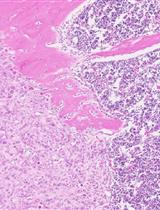

• The Ad-Cre-Luc-mediated ablation of Pten leads to hyperplasia that progresses through prostatic intraepithelial neoplasia (PIN) to adenocarcinoma.

• PIN refers to the non-cancerous growth of epithelial cells in the prostate tissue—not cancer but a precursor of prostate cancer [1].